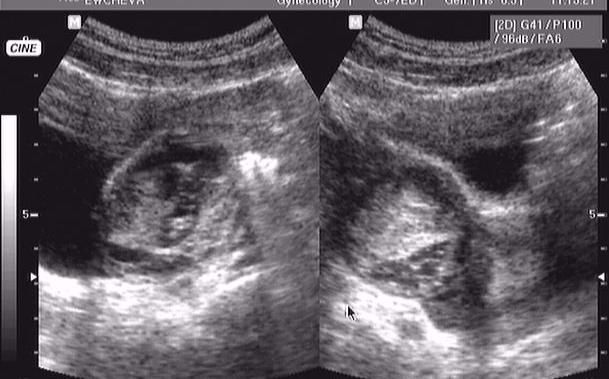

кровоизлияние в кисту яичника

девушка 16 лет, дисменоррея. поступила в хирургию вчера вечером д-з о. аппендицит.